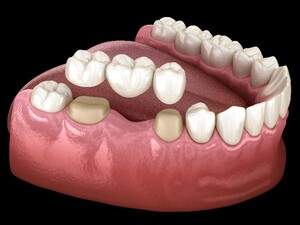

インプラントとは、虫歯や歯周病などの様々な原因により歯が失われてしまったところへ、人工の歯の根=人工歯根(インプラント)をつくり、その上に被せ物を装着する治療法のことです。

インプラントの特徴は、歯根まで再現し骨とインプラントが直接結合することにより、天然歯と同じような見た目・機能の両面において元の自然な状態へ近づくことができ、またしっかり噛むことができます。

| 特徴 | 人工歯根を埋め込み、 その上に被せ物をかぶせる治療。 |

両隣の歯を削り抜歯部位にダミーを置き、 2本の歯で3本の歯の役割をする。 一番後ろの歯には選択できない。 |

両隣もしくは、反対側の歯にバネを掛けて、 人工の歯茎・歯にて補う。 取り外しが必要。 |

抜歯予定の歯に、 親知らずなどの不要な歯を移植する方法。 親知らず・年齢等の条件が必要。 |